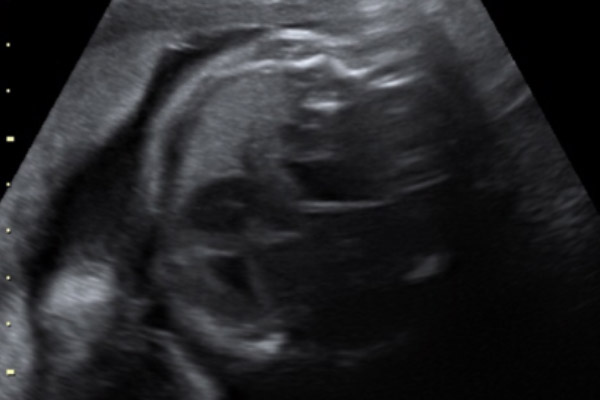

Na ecografia obstétrica morfológica do primeiro trimestre, que é realizada entre 11 semanas e 13 semanas e 6 dias, você suspeita do diagnóstico.

Geralmente, no morfológico do segundo trimestre (entre 18 e 24 semanas) você confirma este diagnóstico.

Quais as estruturas abdominais que herniam no tórax?

Podem herniar estômago, baço, alças intestinais e, em casos mais graves, também o fígado.